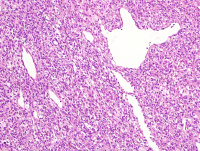

左颊黏膜肿物

性别

女

年龄

63岁

发现左颊黏膜肿物半个月,无明显疼痛

肿物1.5*1.5*1cm,界清,切面实性,红褐色,质软

图3